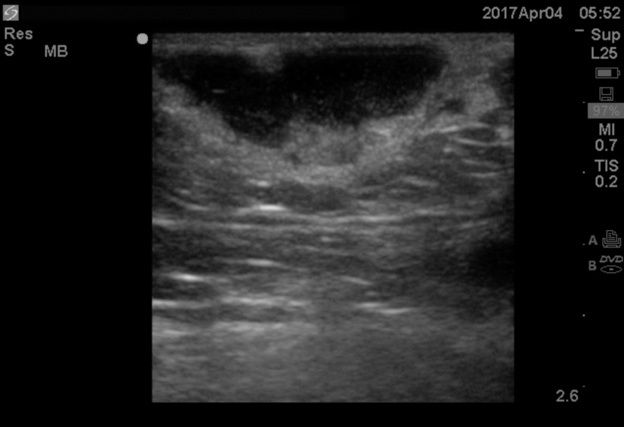

Point-of-care ultrasound can visualize the purulent collection of an abscess. Point-of-care ultrasound reduces failure-to-diagnose rate and decreases the number of inappropriate incision and drainage procedures of cellulitis.20 Cellulitis on ultrasound shows scattered fluid pockets in a cobblestoning pattern (see Figure 2), whereas an abscess will show a distinct fluid collection.21 (See Figure 3.)

Figure 3. Ultrasound of Abscess |

![]() |

Source: Image used with permission from Andrea Kaelin, MD. |